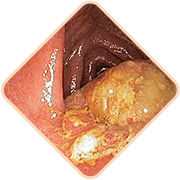

Escucha! ¿Tienes alguno de estos síntomas?

Sensación de pesadez o cuerpo extraño en el recto

Picazón y ardor en el área del ano

Dolor al defecar, caminar y sentarse

Sensibilidad de los ganglios hemorroidales al palpar

Sangrado durante los movimientos intestinales o con esfuerzo